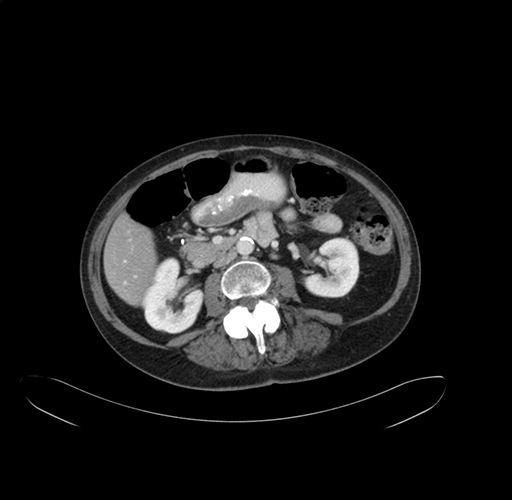

Axial Venous